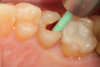

Fig 11. After removal of the existing restorations and associated recurrent decay, both cavities are very deep and there is a pinpoint pulpal exposure on tooth No. 19.

Figure 11